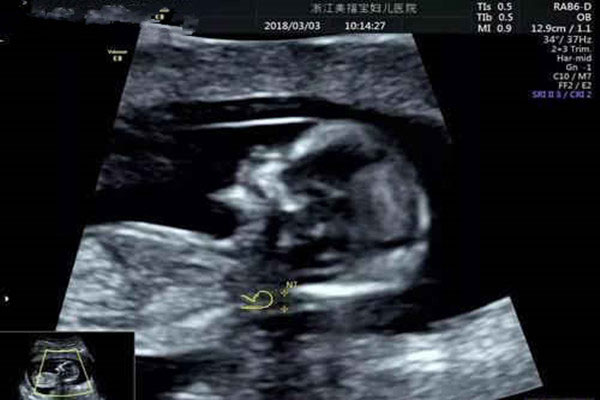

nt检查,是怀孕期间必做的产检项目。网传nt值小于1,大多生女孩;nt值大于2,大多生男孩;nt值在1和2之间的,生男生女的几率各自参半。

nt检查,是怀孕11周后,14周前做产检项目。正常情况下,nt值不超过3毫米,就表示胎儿宝宝发育是健康的。

做nt检查的时间不同,孕妈妈的孕周不同,nt检查的结果标准当然是不一样的。打个比方,孕妈妈11周做的nt检查,数值就小一点,孕妈妈13周做的nt检查,数值自然大一点。

另外,nt检查的结果数值,也会因为胎儿宝宝的姿势和医生的读数,而出现误差和不同。nt数值的变化很随性,同一个孕妇不同时间点测试,结果可能就是不一样的。